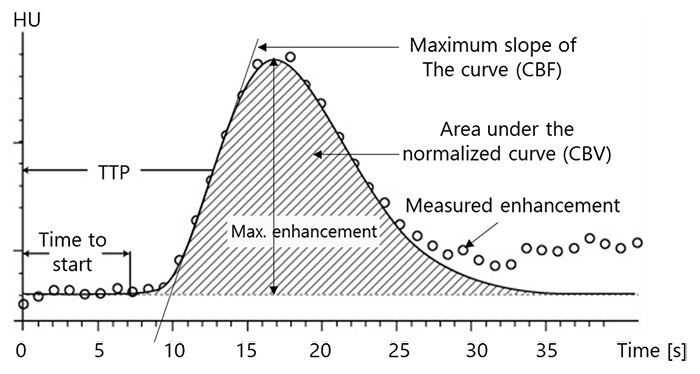

The instantaneous concentration of contrast material within each voxel is calculated by comparing the tissue attenuation at any time point with baseline images obtained before the arrival of the contrast bolus. Combining the measurements drawn from the several time points produces a concentration-versus-time curve (C1) for each voxel. Then a mathematical analysis of C1 for each voxel, generates a number of important parameters of hemodynamic performance, such as CBF, CBV, MTT, and the time-to-peak tissue response.

The Cerebral Blood Volume CBV, is defined as the volume occupied by intravascular blood in any particular section of brain tissue. It is measured in units of milliliters of blood per 100 g of brain.

Theoretically, any Brain CBV can be calculated in a voxel by adding the contrast concentration measure at each time point of the CT. Thus, if the concentration at time point A in a particular voxel is triple that of time point B in a second voxel, the CBV in voxel 1 is 3 times greater than in voxel 2. However, in real conditions the CBV calculation is not accurate because of the scan short duration.

We have mentioned earlier that the CBV calculation is not accurate because of the scan short duration. This is right because a typical perfusion CT requires a contrast injection time of about 10 seconds, followed by only 35 seconds for the bolus to pass from the arm to the brain.

Besides, it is known that some portions of the bolus take a much longer time to reach the brain, thus causing errors in CBV estimation.

An additional cause of error involves the phenomenon of recirculation, which can occur in short-duration scans. Indeed, multiple recirculation passing through the brain may take place during a single perfusion scan, as the initial recirculation of the bolus starts prior to completion of the initial pass. As a consequence, the CBV of any particular voxel may actually measure the summation of multiple passes, overestimating the contrast concentration at that time point.

Underestimation of the tissue concentration can also occur, if the arrival of the bolus is slowed through any or several parts of the brain. Post-processing software, which applies algorithms that overcome the recirculation phenomenon, allows the calculation of regional CBV by integrating the contrast concentration at each of the time points (Ct) over the duration of the scan. Through this approach, scans of longer duration can generate reasonably accurate CBV measurements.

Moving to the 2nd parameter in brain CT perfusion, the CBF is defined as the volume of blood passing through a given amount of brain tissue per unit of time, most commonly milliliters of blood per minute per 100g of brain tissue.

The CBF is calculated because it determines the tissue viability and the neurologic status in any brain disorder CT as it reflects the rate of oxygen and glucose in the blood.

The third main parameter to take into consideration is the Mean Transit Time. MTT is measured in seconds and defined as the average amount of time it takes blood to transit within the blood vessels in a particular region of the brain. In brain imaging, maps of MTT are the most commonly used in clinical situations.

Time to Peak

The last essential parameter used in brain perfusion CT is the time to peak Tmax It is defined as the time at which the contrast bolus achieves maximum amplitude. This measure is calculated in post-processing. The maps that are produced indicate the arrival delay of the bolus in the artery used to derive At, or the time that elapses between AIF and the bolus’ arrival in the voxel in which Tmax is determined.

In practice, Tmax values reflect the time point in which they are sampled. Thus, in a CT perfusion scan where images are acquired every 2 seconds, Tmax maps will have values of 0, 2, and 4 seconds, continuing for the length of the scan.